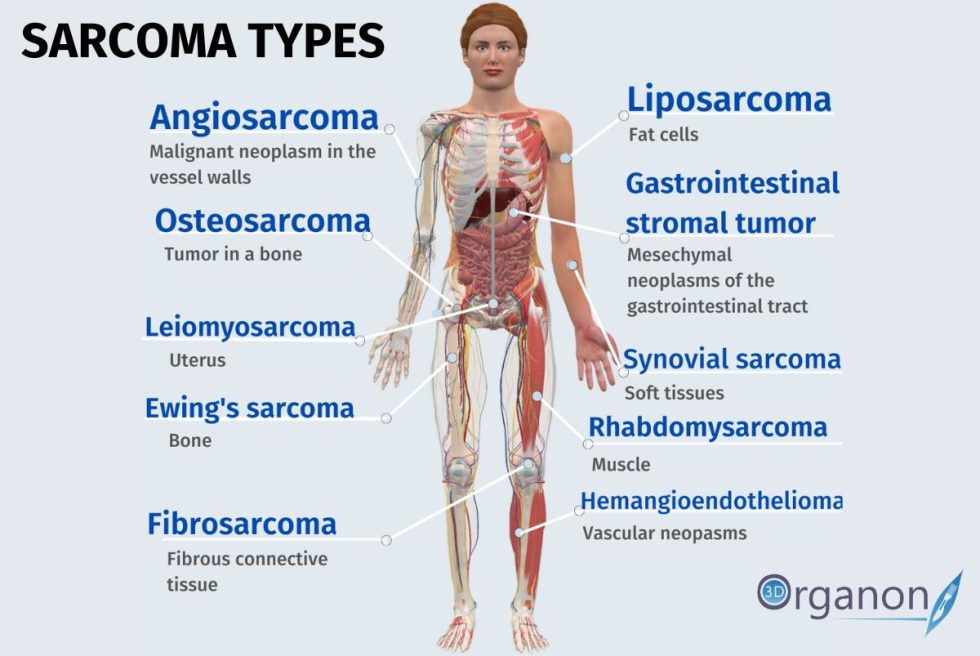

https://www.3dorganon.com/wp-content/uploads/2022/07/sarcoma-types-980x656.jpg

July Sarcoma Awareness Month 3D ORGANON